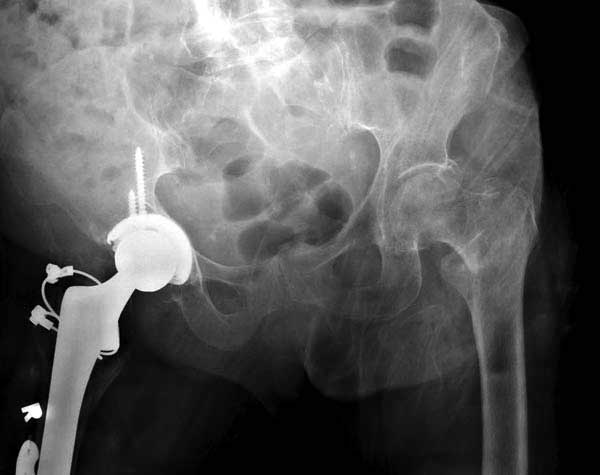

Сеньоры-пэры ревизировали гвоздем, шуруп поставили по той же дорожке, только поглубже. Да еще и bone graft не пожалели. "Результат" уже был через 2 дня.

Если сохранять головку - думаю надо было в валгусе фиксировать перелом гвоздем, или DCS, т.к. все-равно разрезали, чтоб достать DHS.

Бедная бабушка!

Неужели фиксация протеза бесцементная? Да и чашка не запрессована как надо.Грустно(

Эт -ж биполяр:)) Ножка цементная. Страйкеровский Exeter.1

биполярный эндопротез все же не лучший выбор для данной ситуации.судя по снимкам мышечные прикрепления на вертелах утрачены.Возможно здесь подошла бы более стабильная конструкция.Ваше мнение?

а куда делся фрагмент большого вертела? Очевидно,

Если среднеягодичная мышца не рефиксирована, то ничто не держит протез во впадине и это закономерный результат.

Вторая операция- это фаза сохранения головки бедра. Желательно приложить все усилия и сохранить головку, но, как видно, “фиаско” продолжается. Здесь вместо нейтрализации сил между медиальной и латеральными сторонами была попытка удержать варус. Варус не удержать ни деротационными шурупами о котором говорили и не костными стружками вбитые в шейку, потому что вся нагрузка упирается в головку.

Как отметил Евгений, 95 degree Blade Plate Fixed Angle device расчитана на восстановление взаимоотношении между головкой и диафизом, а все остальные фиксаторы (Gamma, Afifuxus и др.) работают за счет нагрузки в верхнем полюсе головки. Верхний полюс успели разрушить, и в головке единственное место, который смог бы удержать широкий клинок конструкции, это медиально-низкий сегмент. После установки клинка засчет дистракции можно удлинить конечность на 15мм, а добавленный в дефект ауто-графт закончил бы дело.

Третья операция-продолжения усилии “синьорами пэрами” по разрушению нормальной анатомии. Крест на головку! По видимому возраст позволяет биполярную конструкции, и при дефекте calcar пошли на обычный цементный. Ягодичные мышцы потеряли связь с вертелом, т.е. отсутствует верхний удержатель, и результат “a Big Screw Up!” Снимки вызывают головокружение!

Если хирурги не устали от своих “творчеств”, тогда можно ре-оперировать с calcar replacement stem, и собрать остаток ягодичных мышц. Глубина и отстутствие артроза позволяет применить любой, биполярный или тотальный, хотя принять решение можно после ревизии ацетабулума.